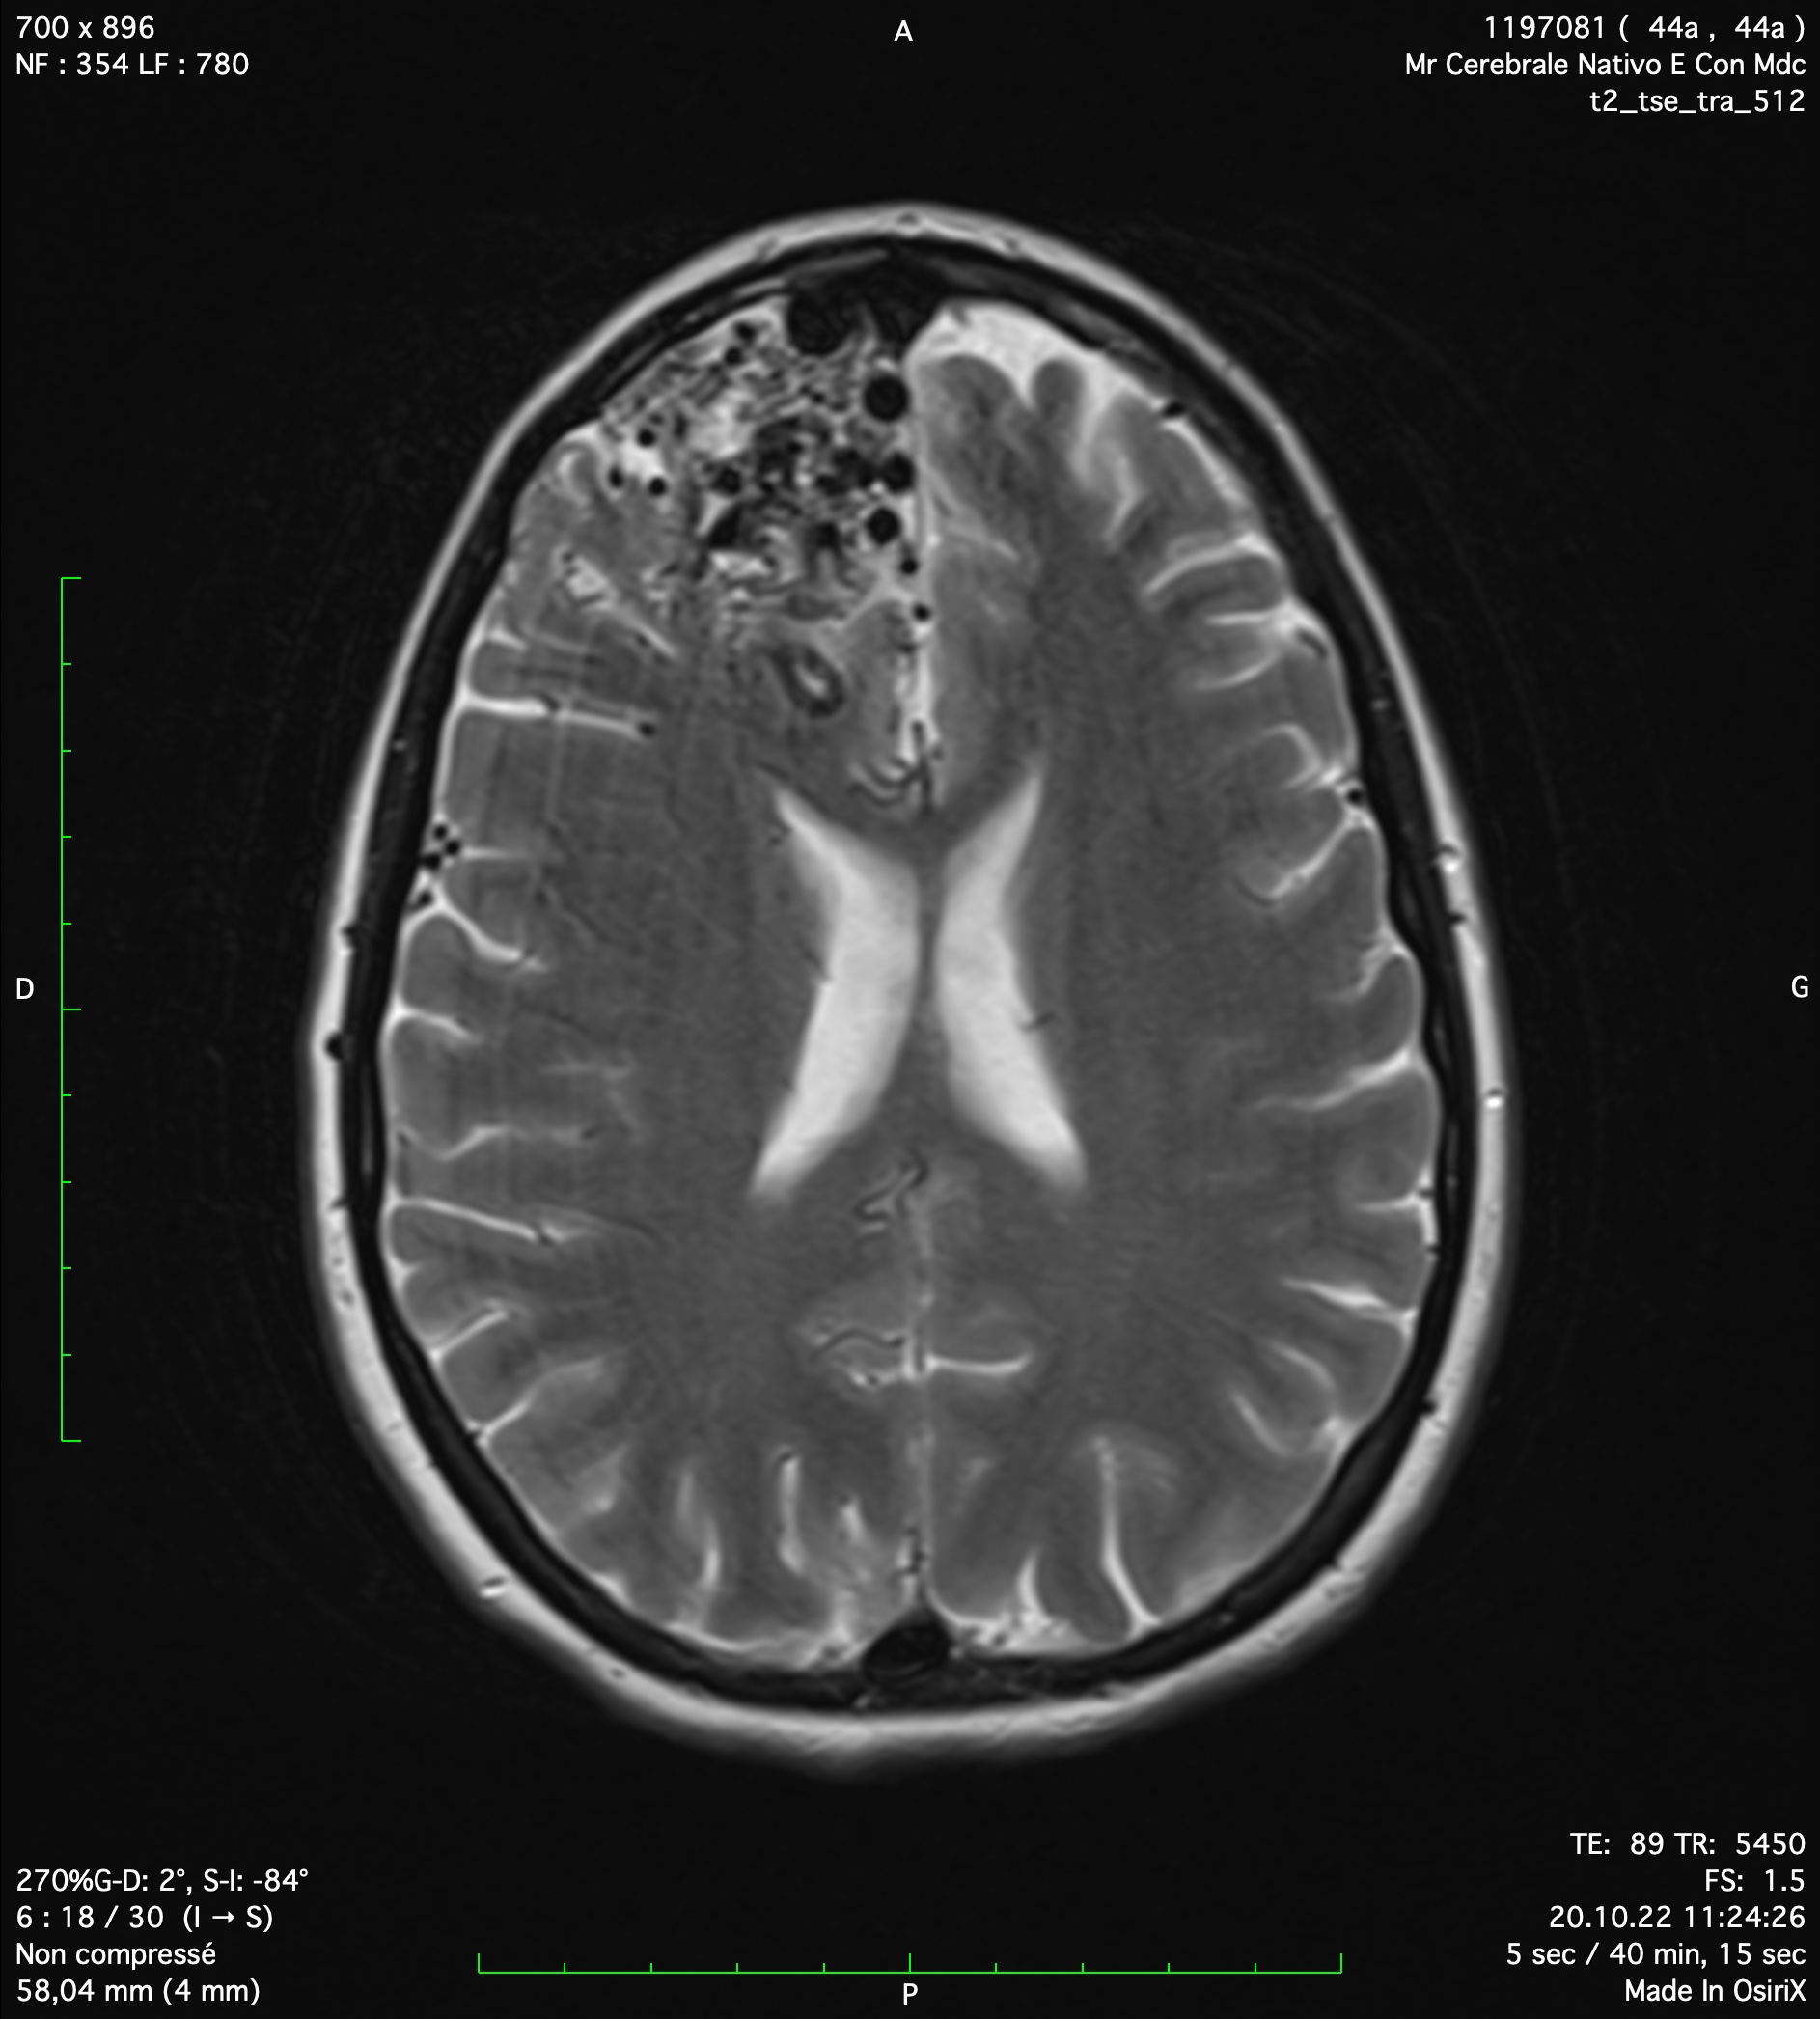

A cavernoma or cavernous angioma is a vascular pathology of the central nervous system which is defined as a venous mass in the cerebral parenchyma or in the medulla. Most frequent clinical signs are seizures, motor deficit and headache. The classical treatment is the microsurgical resection under general anesthesia. Alternative treatments as radiotherapy are limited to inaccessible lesions.

Cerebral cavernoma

Fortunately, most of cerebral cavernomas are asymptomatic and stable. In these cases, there is no indication for a treatment and only a radiological follow-up is necessary. Dr Robert and Dr Bonasia have an important experience in follow-up and surgical treatment of cerebral cavernomas. This is a treatment they propose at Clinique La Source in Lausanne.